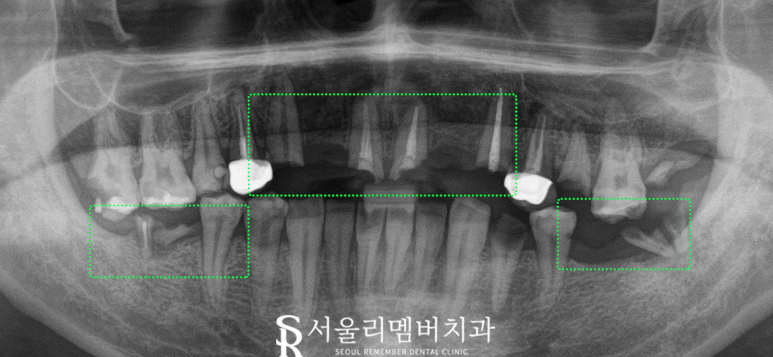

x-ray를 보면

위쪽은 부러진 앞니와

아래쪽도 거의 소실된 어금니를 볼 수 있습니다.

그리고 치조골이 퇴축되어서

위쪽 치아들은 흔들리기까지 합니다.